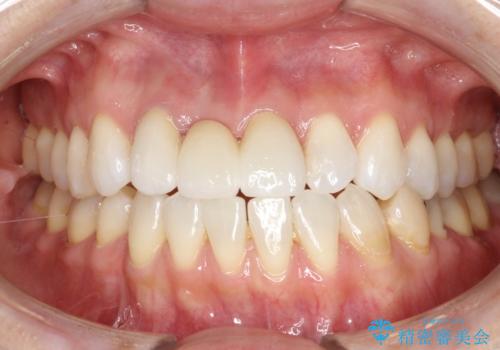

[フルジルコニアクラウン] 老朽化した銀歯を白く

![[フルジルコニアクラウン] 老朽化した銀歯を白くの症例 治療後](https://seimitsushinbi.jp/wp/wp-content/uploads/2020/05/60951366446f010978e24aba6c35e27e-500x350.jpg?v=1588518777)

前歯の変色 根管治療と高品質セラミック歯科治療